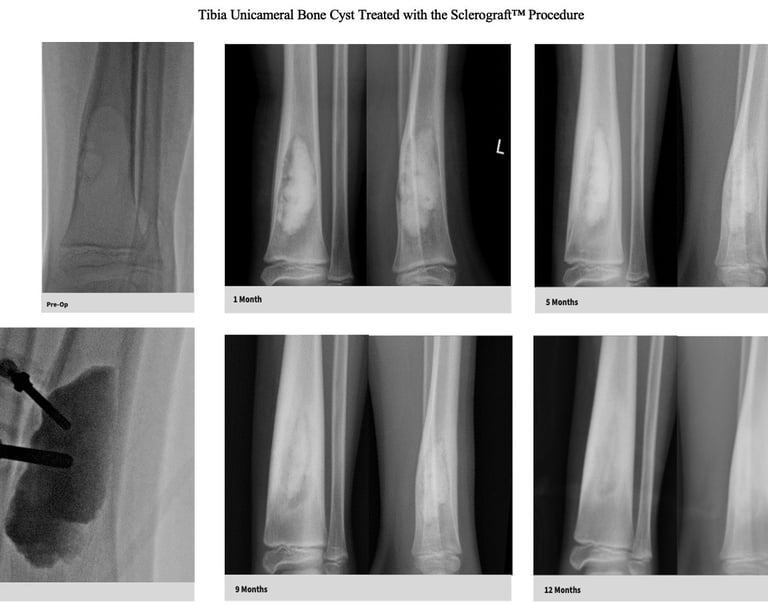

Gallery

Explore our educational resources and images

The Sclerograft procedure is a minimally invasive outpatient procedure used to treat bone cysts.

Utilizing needles, chemical sclerosis destroys the cyst wall and regenerative bone graft is injected via the needles to expedite bone healing.

The doctor uses imaging guidance (like X-ray or ultrasound) to guide needles into the cyst.

Chemical sclerosis using chemicals like doxycycline are washed through the cyst to kill the cyst wall lining

Regenerative bone graft is then injected through the needles and the needles are removed. The bone graft is temporary and is eventually reabsorbed by the body.

Quick recovery and bone formation seen between 6 weeks to 3 months

Low recurrence rates

Proven success in both UBCs and ABCs

The long term follow-up with x-rays is critical because of the possibility of bone cyst recurrence. Generally, if a recurrence occurs, it tends to be noticeable by the 6 month mark